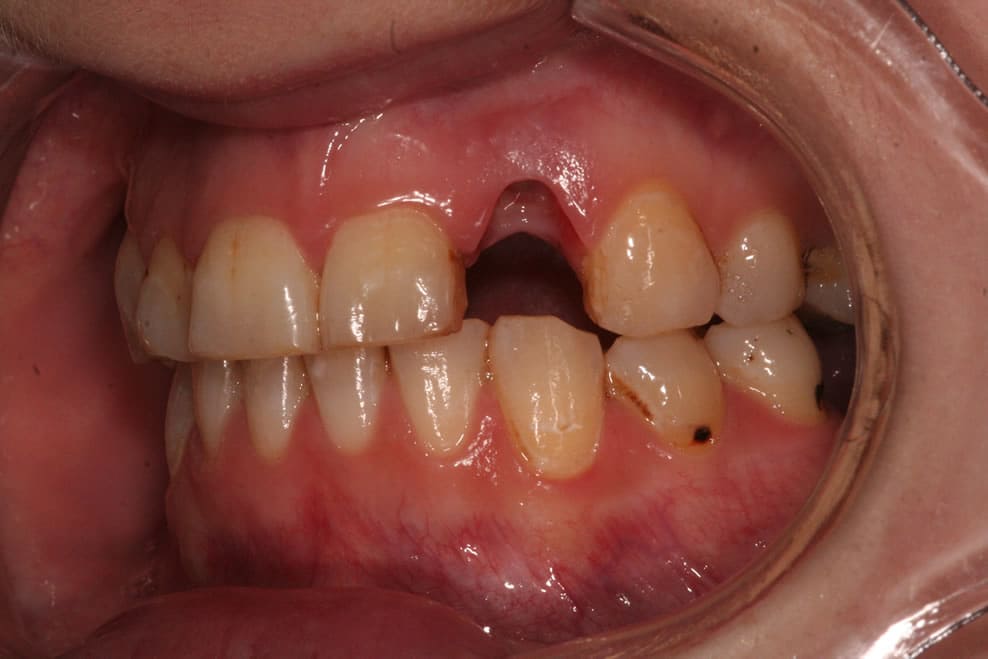

IMPLANTS FOR SINGLE & MULTIPLE MISSING TEETH

Dental implants are the best-known treatment to replace single or multiple missing teeth because they feel and behave just like natural teeth. After a while you won’t be able to tell the difference – even forgetting that they are there.

The procedure to place implants and replace a missing tooth or multiple teeth is straightforward as there is little need to treat surrounding teeth. Once a crown is placed over the implant it will appear indistinguishable from the natural teeth.